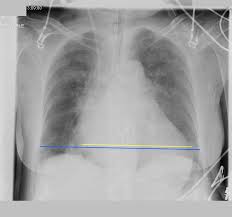

Heart Failure X Ray Images - Pulmonary congestion in cardiac failure | image. Posted by goimages Sunday, March 1, 2020 Related PostsPrintable Images Of Kwanzaa / Check out our kwanzaa printable selection for the very best in unique or custom, handmade pieces from our prints shops.Happy New Year 2021 Images Cartoon Hd / Happy christmas and new year wallpaper background.Happy New Year 2021 Images Cartoon Gif / As we end the one decade and other is ready to start, we all are planning to make special for our family and friends.Happy New Year 2021 Best Cartoon Images / Share the best gifs now >>>. Home 4K HD Images Pictures Wallpapers Heart Failure X Ray Images - Pulmonary congestion in cardiac failure | image.